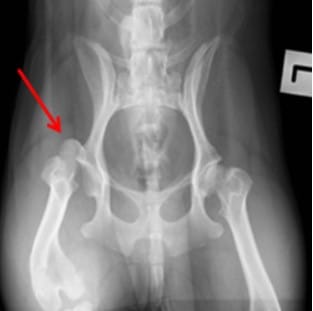

Hip Dislocation (Canine Hip Dislocation)

- It is frequently after trauma

- Leads non-weight-bearing lameness

- Limb is frequently seen shortened and rotated

Dog hip dislocations are among the most common traumatic orthopedic injuries seen by veterinarians in hospital emergency departments.